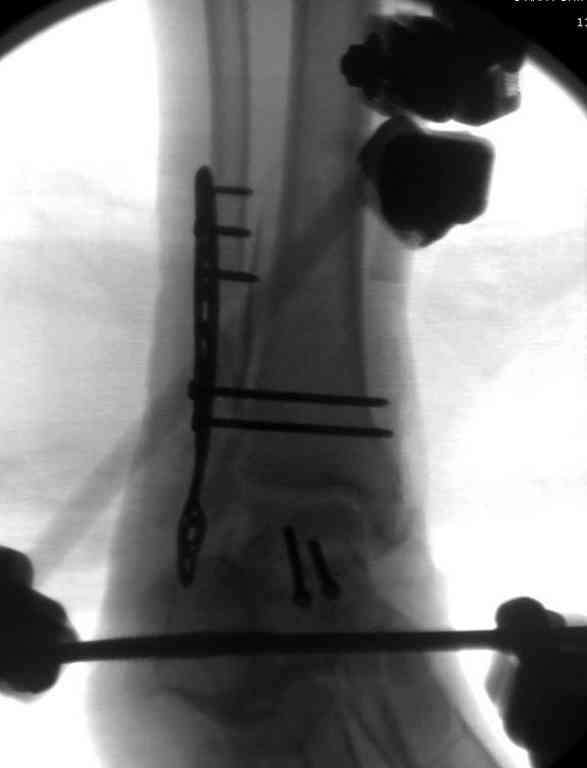

Вчера провели фиксацию.

Из-за многооскольчатости дистальной части малоберцовой, где невозможно было провести фиксацию шурупами, перелом зафиксирован подпирающей пластиной, которая должна служить дополнением отсутствующей дистальной части малоберцовой (lateral cortex substitute).

Для стабильности два шурупа на синдесмоз.

Медиальную рану с приближенными краями продолжаем вакуумировать (KCI). Наружный фиксатор оставлен на пару недель, надеюсь, небольшая рана будет гранулировать и закроется без кожной пластики. Фиксация медиальной ложыжки не планируется.